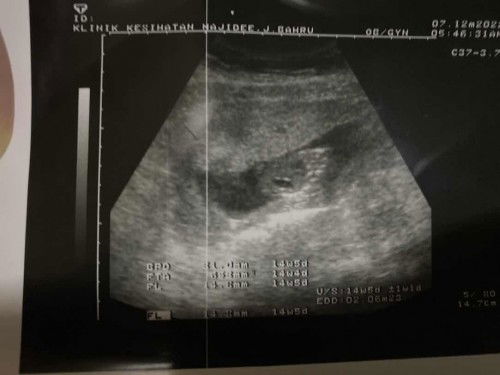

Siapa tahu ni bahagian mana ya? saya tak faham scanning 14 weeks dr Kk

Siapa tahu tengok Scan 14week

Saya pagi tadi ada bleeding agak banyak, tapi dah pergi kk dan dah pergi hospital Alhamdulillah setakat ni baby sihat je. cuma risiko keguguran tu still ada. saya dpt ubat kuatkan rahim. Ni 2nd Baby after first gugur tahun 2020. Doakan saya dengan baby sihat sihat ya 😌 Saya tak faham dgn gambar scanning tu kalau ada sesiapa faham boleh bagitahu bahagian mana tu ?